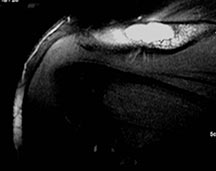

- May arise from any bone and any site within a bone (epiphyseal, metaphyseal, diaphyseal)

- Radiographically variable appearance: may appear benign (geographic) or malignant (permeative or moth eaten)

Sites:

- Humerus

Radiographic Presentation